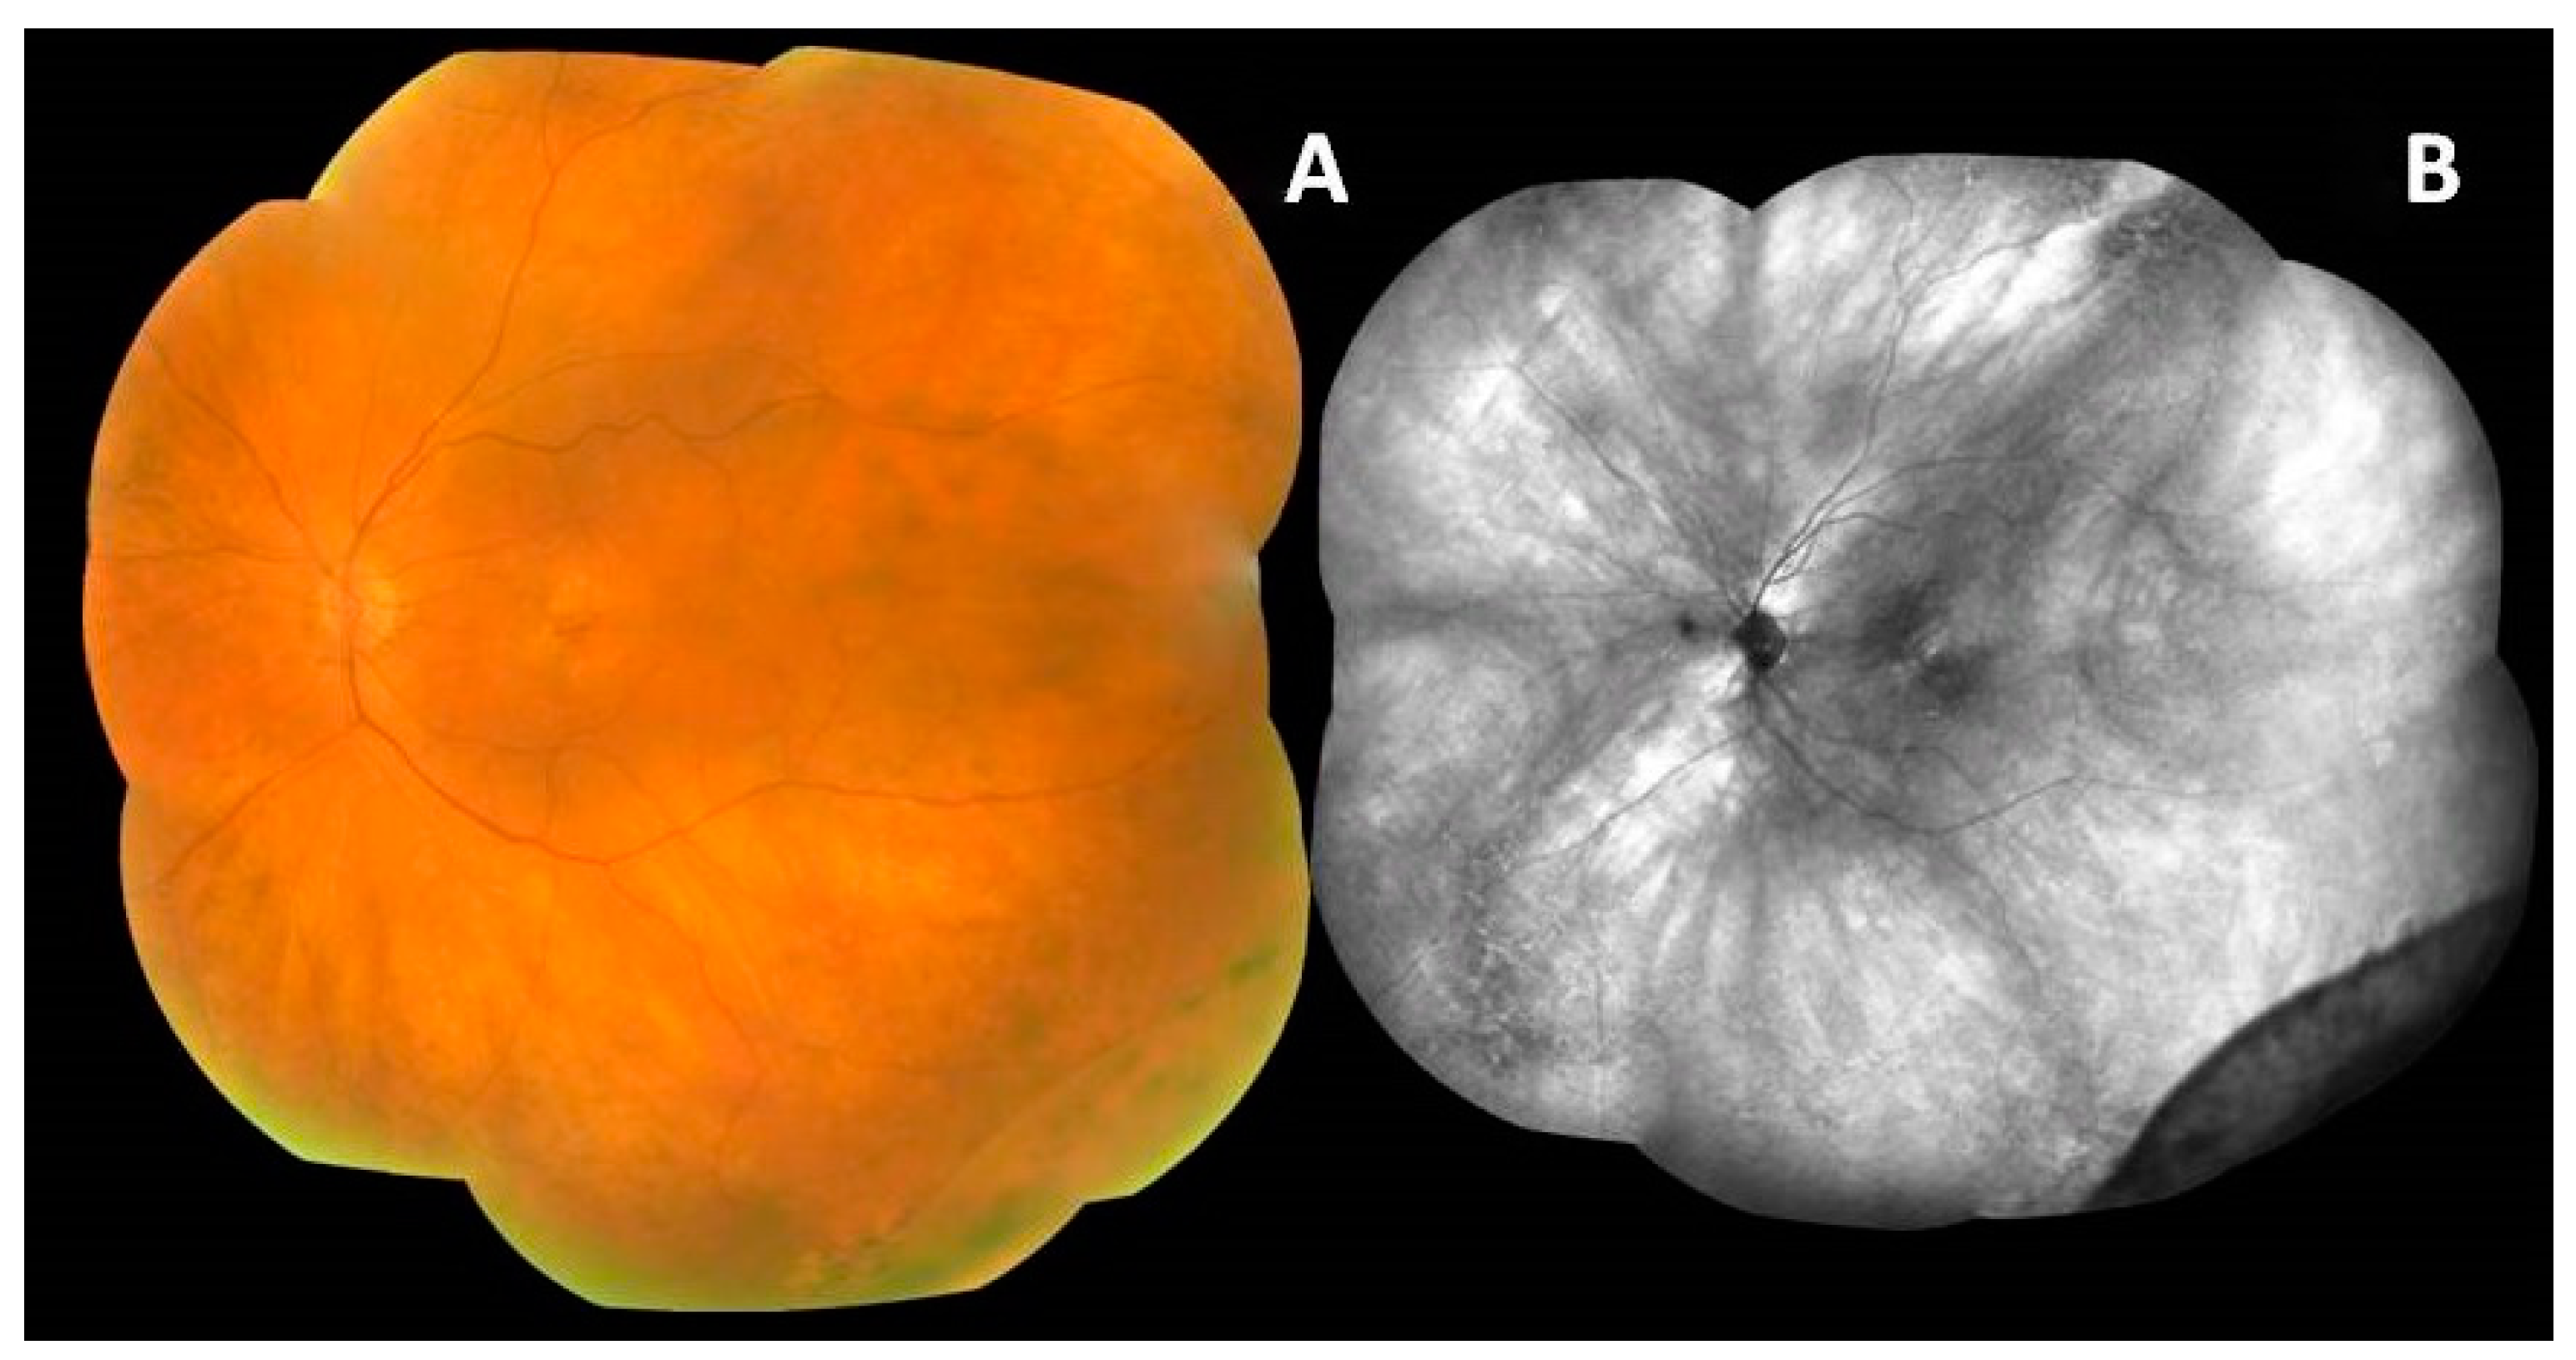

2. Retinal Function Assessment

3. Peripheral Retina in Multimodal Imaging

4. Function of the Peripheral Retina in AMD